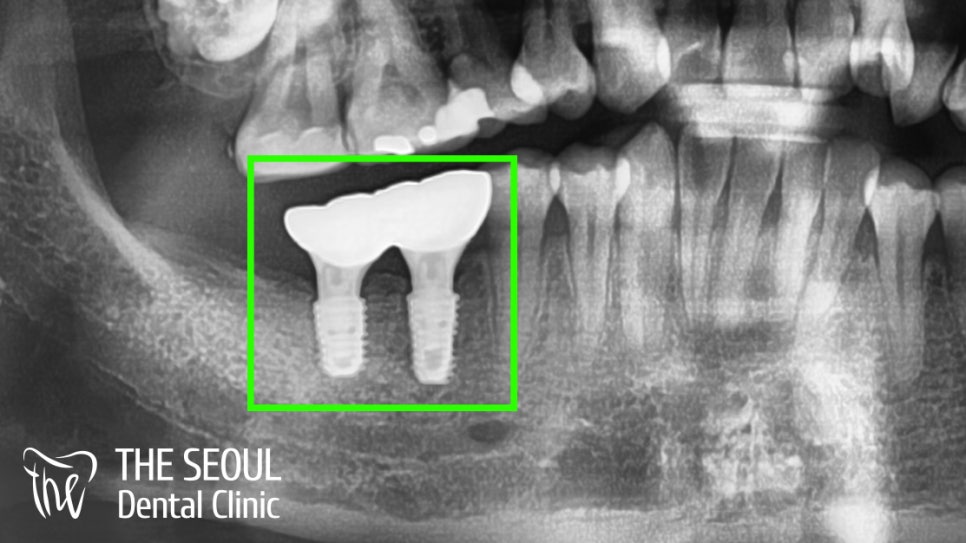

디지털 방식을 이용하여 식립하는 것으로 계획했습니다.

디지털 방식이기 때문에

컴퓨터 분석을 통해 어디에 심으면 좋을지!

주요 조직과의 거리는 얼마나 될지!

교합 및 컨택은 잘 맞고 있는지!

꼼꼼하게 확인을 했습니다.

자, 분석된 내용을 토대로 식립을 진행해야겠죠?

계산된 식립 위치에 맞게 안정적으로 심어져 있는 모습입니다.

치유 지대주와 픽스처의 연결 부위도

매끄럽게 이어지는 것이 관찰됩니다.